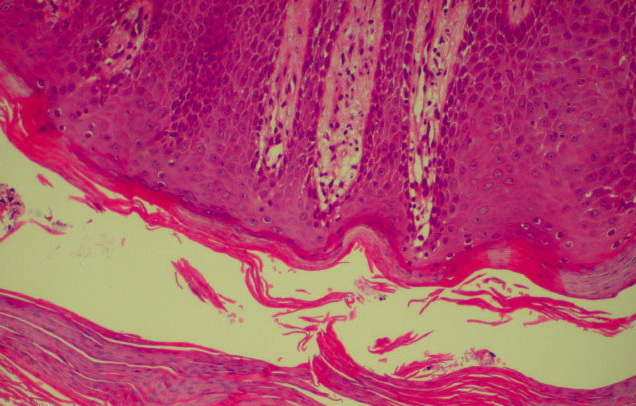

Histopathology Whereas in ordinary psoriasis the spongiform pustule of Kogoj is a very small micropustule and is seen only in early, active lesions, it occurs as a macropustule in all variants of generalized pustular psoriasis and represents their characteristic histologic lesion. The spongiform pustule forms through the migration of neutrophils from the papillary dermal capillaries to the upper layer of epidermis, where they aggregate within the interstices of a spongelike network formed by degenerated and thinned epidermal cells . As the size of the pustule increases, the epidermal cells in the center of the pustule undergo complete cytolysis so that a large single cavity forms . At the periphery of the pustule, however, the network of thinned epidermal cells persists for a much longer time. As the neutrophils of the spongiform pustule move up into the cornified layer, they become pyknotic and assume the appearance of a large Munro abscess . |

In addition to the large spongiform pustules, the epidermal changes in generalized pustular psoriasis are very much like those seen in psoriasis vulgaris, consisting of parakeratosis and elongation of the rete ridges. The upper dermis contains an infiltrate of lymphocytes, and neutrophils can often be seen migrating from the capillaries in the papillae into the epidermis . The oral lesions show the same spongiform pustule formation as those seen on the skin . In the healing stage, the lesions of all types of generalized pustular psoriasis may present the same histologic appearance as ordinary psoriasis . |